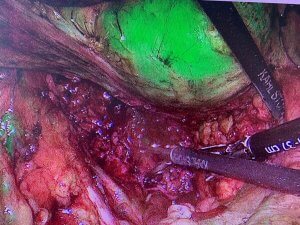

GASTRECTOMIA LONGITUDINALĂ LAPAROSCOPICĂ

Gastrectomia longitudinală laparoscopică este la ora actuală cea mai raspândită soluție chirurgicală bariatrică, datorită progreselor tehnologice importante și a complicațiilor post-operatorii scăzute.

Este cunoscută ca și micșorare a stomacului și constă în secționarea longitudiană și îndepartarea unei porțiuni de aproximativ 80% din volumul total al organului.

Acționează atât prin reducerea capacității de rezervor a stomacului cât și prin scăderea secreției “hormonului foamei” (GRELINA) sintetizat de peretele gastric.

Este varianta preferată în cele mai multe cazuri datorită rezultatelor rapide și spectaculoase privind scăderea ponderala care se menține în timp, dar și a recuperării ușoare și reintegrării socio-profesionale rapide.

De asemenea, acest tip de procedură bariatrică nu modifică circuitul alimentelor prin tubul digestiv și presupune mai puțină agresiune asupra stucturilor și nu modifică semnificativ absorbția vitaminelor și mineralelor.